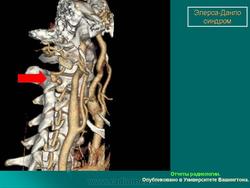

3. Васкулярный тип.

Наследуется по аутосомно-доминантному типу. Основные диагностические критерии: тонкая, прозрачная кожа, разрывы стенки артерий, кишечника и/или матки,обширные кровоизлияния, характерный фенотип. Дополнительные диагностические критерии: гипермобильность мелких суставов, разрыв сухожилий и мышц, косолапость, варикозное расширение вен с ранней манифестацией, артериовенозные каротидно-кавернозные фистулы, пневмоторакс/пневмогидроторакс, атрофия десневого края; положительный семейный анамнез, случаи внезапной смерти у близких родственников (многие пациенты не доживают до 50 лет из-за разрыва артерий или, что реже кишечника). Наличие двух и более главных критериев с большой вероятностью указывает на диагноз васкулярного типа СЭД и является показанием для лабораторной диагностики. Нередко отмечается характерный фенотип (узкий нос, тонкие губы, натянутая кожа, впавшие щеки и экзофтальм, обусловленный, в основном, снижением подкожно-жирового слоя). Надо отметить, что такой фенотип характерен для взрослых больных, а у детей он практически не выражен. Гипермобильность суставов обычно ограничена суставами пальцев. Максимальная частота спонтанных артериальных разрывов приходится на третью-четвертую декады жизни, но они могут возникать и раньше. Чаще всего вовлечены артерии среднего калибра. Беременность и роды могут осложняться разрывом матки и маточными кровотечениями, а также разрывом влагалища и промежности. Именно артериальные разрывы являются наиболее частой причиной внезапной смерти. Поэтому в качестве диагностических мероприятий рекомендуются, по возможности, неинвазивные процедуры. При этом типе СЭД сравнительно хорошо изучены изменения на молекулярно-белковом уровне. Этиологическим фактором являются мутации в гене коллагена IIIтипа.